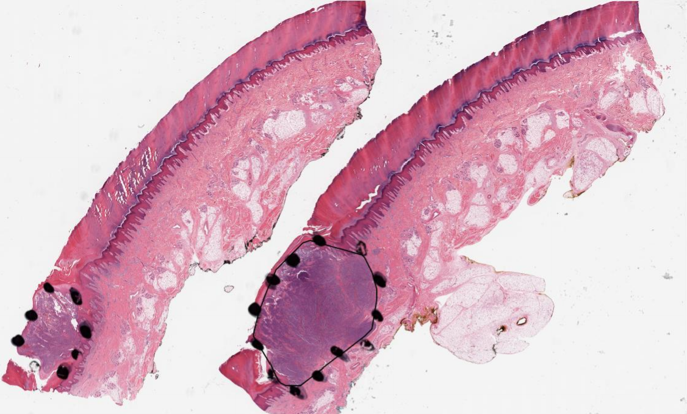

Explanations for the figures. Figure 2 shows one representative sample of annotations (black dot regions) as well as without annotations. Visualization maps of two samples from the melanocytic skin tumor dataset are shown in figure 3 and figure 4. Figure 3 shows the three types of figures of the largest ROI region from melanoma found by the proposed method. Figure 4 is the same for the nevus sample. The overlap map highlights top-ranked patches in a WSI and masks other area with a transparent blue color. The percentage of highlighted patches equals (the annotated ratio). The boundary map shows the boundary of the largest ROI cluster based on the highlighted patches, where the highlighted patches are clustered by OPTICS algorithm from Ankerst et al. (1999). The last one is a heatmap where red covers regions that have high predicted scores and blue covers regions that have low predicted scores.

(a) Boundary of the largest predicted ROI region

(b) Overlay

(c) Heatmap